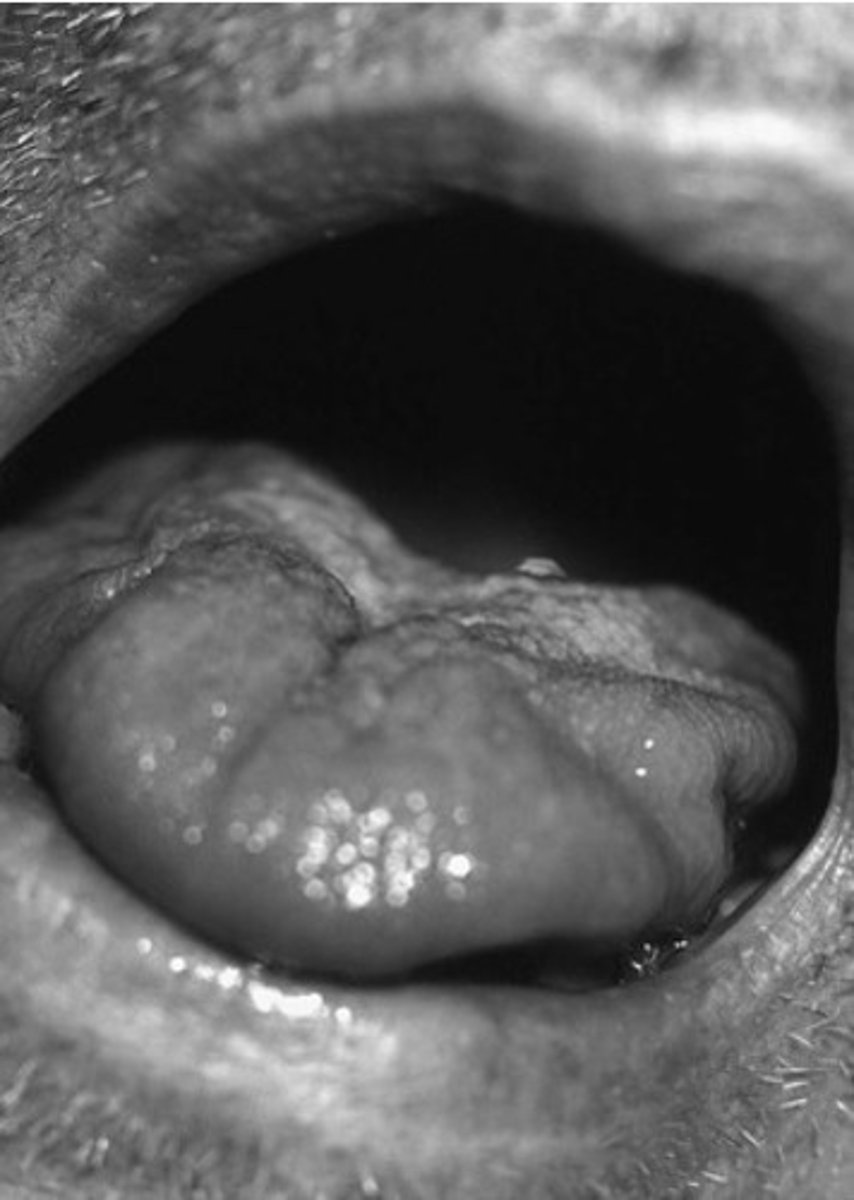

James has neurogenic dysphagia. During your cranial nerve exam, you ask him to open his mouth. What does this picture tell you about his tongue condition?

Tongue atrophy

Based on the tongue picture from the previous question, which level of the nervous system is more likely involved?

Lower motor neuron